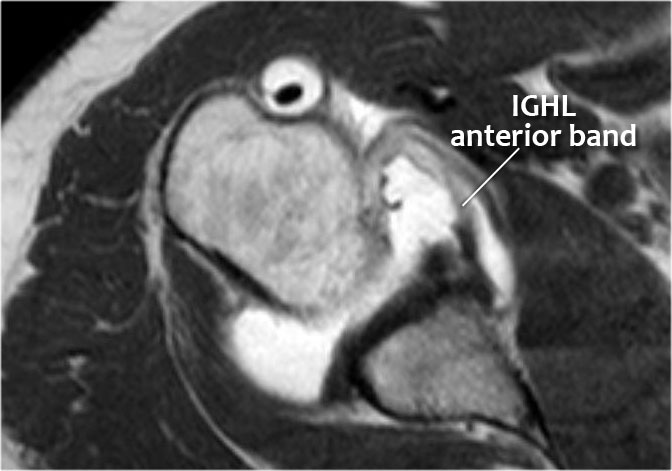

Hình MRI khớp cản từ mặt phẳng đứng dọc cho thấy sự lan rộng lên trên của đường rách Bankart.